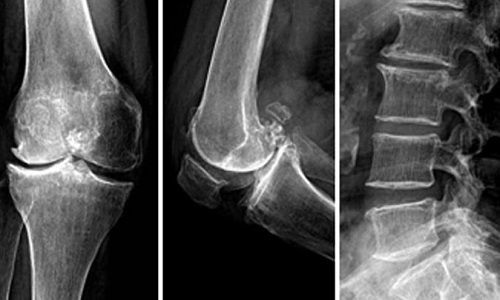

约半数患者出现关节疼痛肿胀、关节积液。以膝踝关节受累多见,尚可累及肘腕、掌指关节和跖趾关节,一般呈不对称性,疼痛以夜间为主,表现为关节轻度酸痛乃至剧烈疼痛。体征包括关节局部发红、发热、触痛肿胀、关节积液和活动受限,也有表现为无痛性关节积液。在没有大量肌肉复盖的部位,由于长骨骨膜新骨形成,可致前臂或小腿日益增粗,腕及踝关节亦相应粗大。

有杵状指(趾)、恶性突眼及胫前黏液性水肿,X线检查示掌骨骨膜下新骨形成,多发于甲亢治疗引起甲状腺功能减低时。有明显的甲亢病史,可资鉴别。

骨改变包括骨膜水肿、炎细胞浸润,随后有骨膜增厚、骨样基质沉着、矿化、新骨形成,骨皮质因与骨膜新生骨连接在一起而增厚。